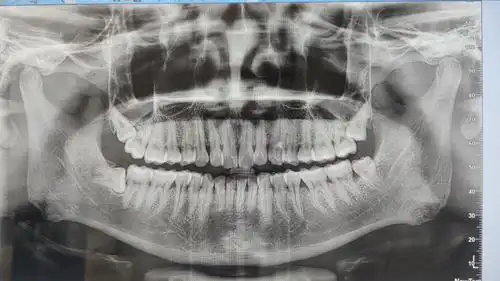

今天的牙片

刚刚拍的牙片

医生看到我的牙片沉默了并叫我好好爱护牙齿

洗牙的时候偷偷用手机拍下了我的牙片,不知道怎么样,自我感觉还挺正的

给大家看看我的牙片